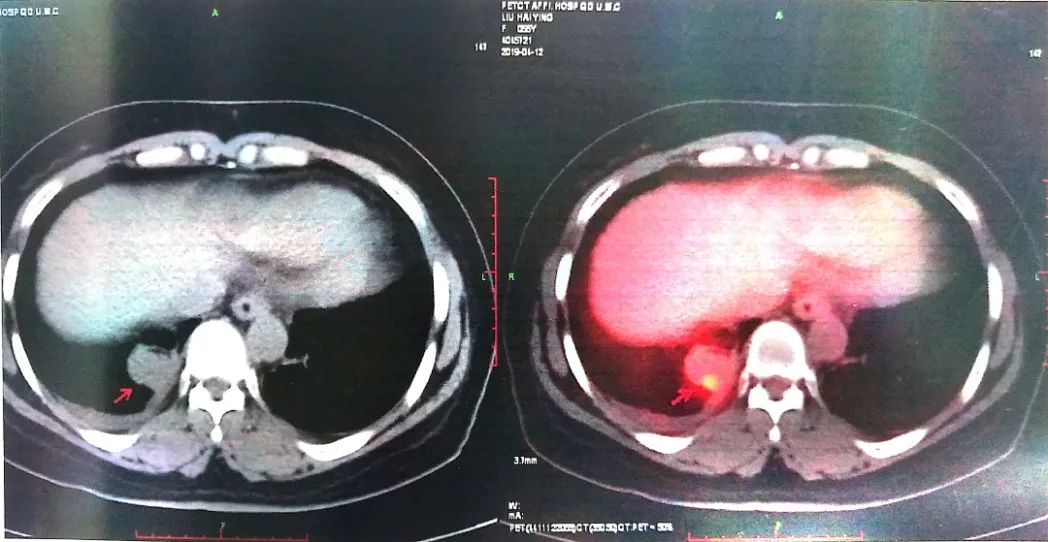

2019-04-12 PET-CT显示①右肺下叶后基底段胸膜下软组织密度肿块(大小26*30mm)。

②左肺下叶纵隔旁软组织密度肿块(大小28*31mm)。

③双肺门、纵隔内隆突下、气管旁、主肺动脉窗、血管前间隙、右侧颈部Ⅴ区及锁骨区多发增大淋巴结。

至此为止,患者的诊断为:肺恶性肿瘤 小细胞癌 广泛期 cT4N3M0 IIIC期(病灶1:右肺下叶,病灶2:左肺下叶),此时先给予标准化疗方案,EP方案:依托泊苷100mg/㎡  d1-3+顺铂75mg/㎡ d1-2 q21d*2。结果如下: